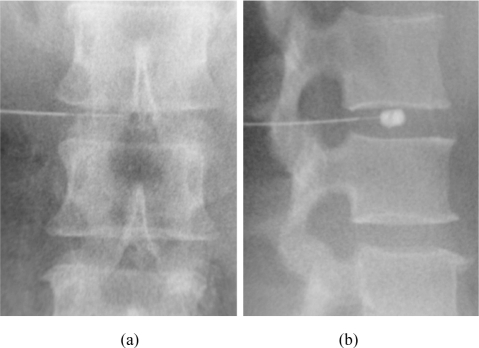

4. RF probe deployment: The probe is deployed to the midline of the vertebral body where the BVN is located

5. Ablation: RF energy is applied to create a lesion that ablates the BVN

Bipolar RF Lesion:

• The bipolar RF electrode is positioned so its midpoint is at the center of the target zone

• Standard lesion protocol: 85 degrees C for 15 minutes, or targeted coagulation at 75 degrees C for 7 minutes